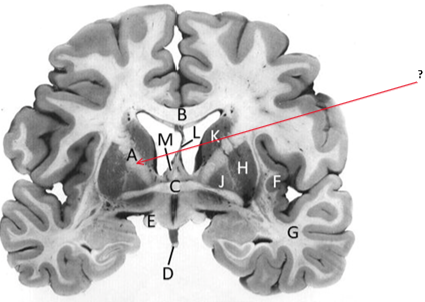

Name this and state its function.

Corpus Callosum.

Putamen.

Name this, state its function, pathways and cellular components.[5 marks]

Caudate nucleus.

Medium spiny neurons utilising GABA and some Cholinergic.

From cortex–>CN–>hippocampus, Gp and thalamus.

Septum pellucidum.

Fornix.

Anterior commissure.

Interconnects:

Infundibular stalk.

Insula.

Name this, state its function, components[2] and the difference in pathways.

Internal capsule.

Anterior limb:

Posterior limb:

Corticospinal tracts and corticopontine tracts: